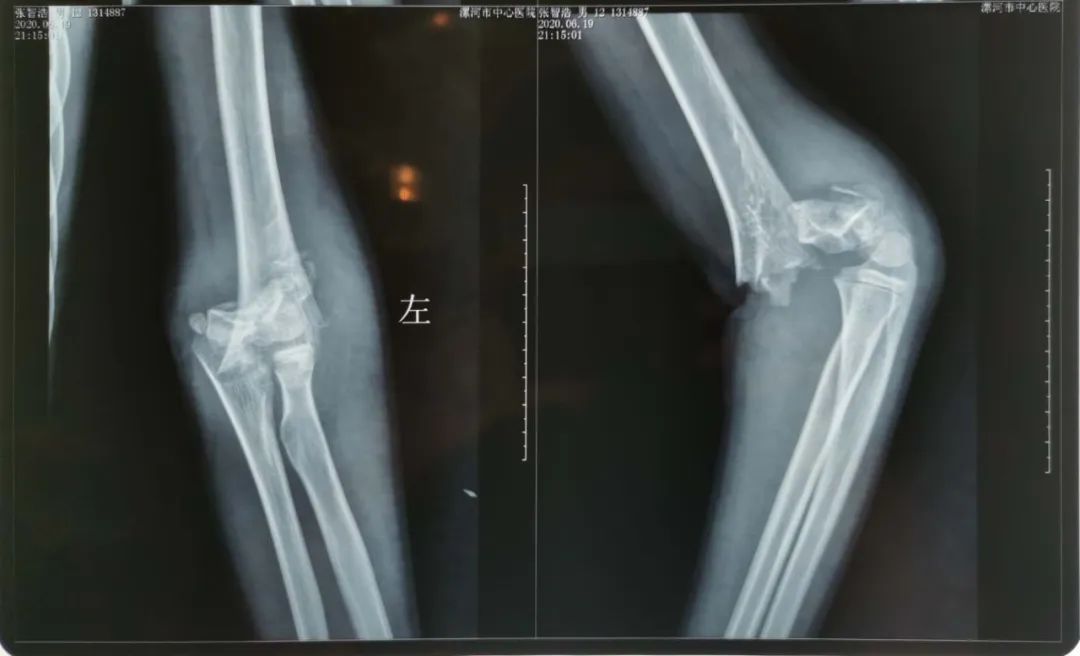

李海乐接到患者后立即进行了全面专科查体,发现患者左上肢肘部极度肿胀,外观畸形,上臂前侧近肘部可见骨折断端外露,活动有骨擦音,桡动脉搏动消失并左手麻木,屈指不能,指甲苍白。经过影像学检查示为“左侧肱骨髁上粉碎性骨折并侧方短缩成角移位”。

凌晨1点半,患者完成术前准备,推入手术室。凌晨2点,麻醉科吴鹏医师快速评估患者麻醉风险后实施麻醉,刘跃华带领助手李军伟及李海乐对患者进行了手术。术中探查见患者左肱骨髁上粉碎性骨折,断端移位造成正中神经牵拉并部分挫断,肱动脉受压并痉挛收缩,肘部肌肉及肌腱组织受损。

术中解除血管神经卡压并修复挫断神经,桡动脉恢复搏动。手法复位肱骨髁上骨折断端,在术中C臂导航下进行精准克氏针固定,骨折断端近解剖复位,逐层缝合术区切口,石膏托固定。凌晨2点40分,手术结束。